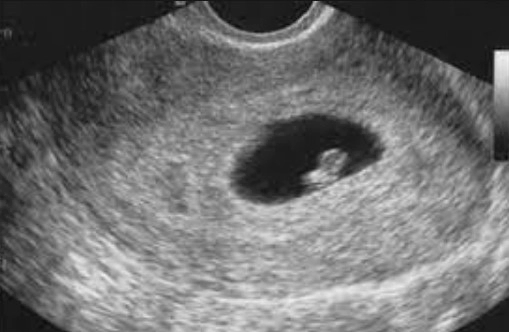

아기집(자궁)의 크기

임신 6주차에는 아직 자궁이 크게 팽창하지는 않습니다. 대체로 자궁은 피부 아래에서 손으로 느끼기 어려울 정도로 작습니다. 그러나 이 시점에서 자궁 내부의 변화는 두드러집니다. 자궁 내부에는 자궁 내막이 형성되어 태아를 보호하며, 착상 후에는 자궁 내막이 아기와 엄마를 연결하는 역할을 하는 태반으로 발달합니다.

초음파

임신 6주차에는 초음파를 통해 태아의 심장 박동을 확인할 수 있습니다. 초음파는 또한 태아의 위치와 성장을 확인하는 데 사용됩니다.